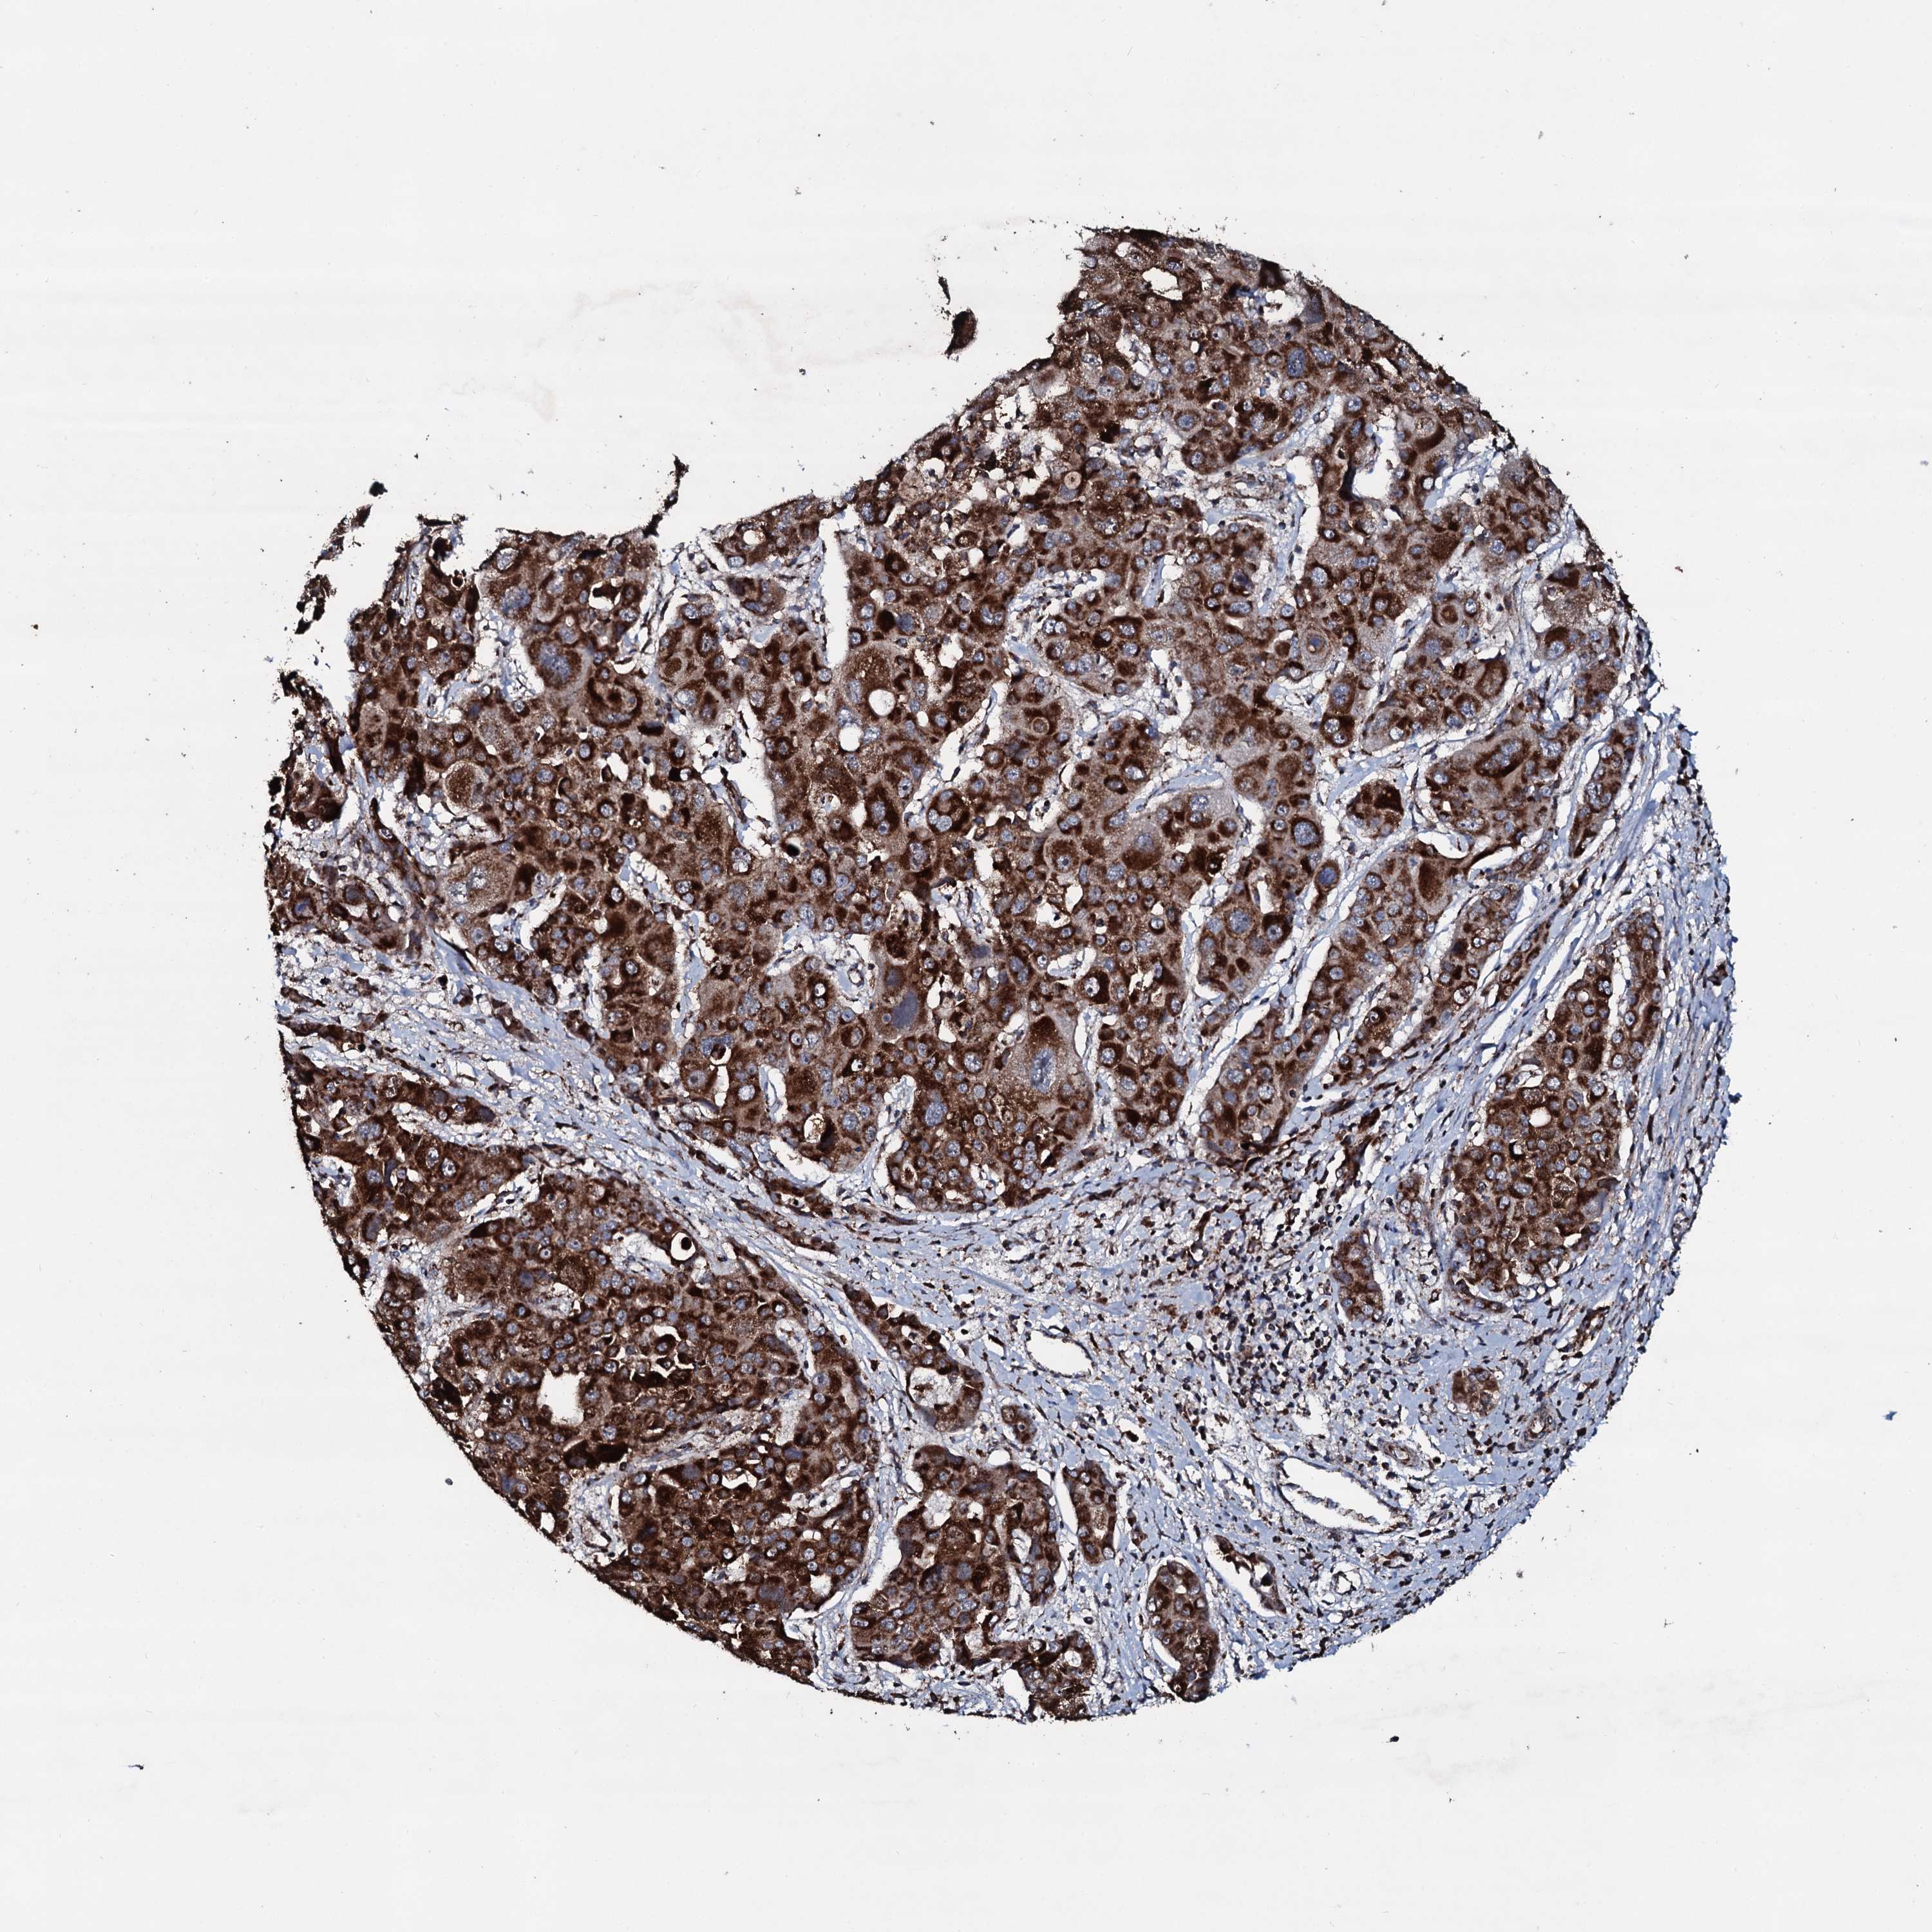

LIVER CANCER - Protein expressioni

A mouse-over function shows sample information and annotation data. Click on an image to view it in a full screen mode. Samples can be filtered based on level of antibody staining by selecting one or several of the following categories: high, medium, low and not detected. The assay and annotation is described here.

Note that samples used for immunohistochemistry by the Human Protein Atlas do not correspond to samples in the TCGA dataset.

Antibody stainingi

Antibody staining in the annotated cell types in the current human tissue is reported as not detected, low, medium, or high, based on conventional immunohistochemistry profiling in selected tissues. This score is based on the combination of the staining intensity and fraction of stained cells.

Each image is clickable and will lead to virtual microscopy that enables deeper exploration of all samples and also displays staining intensity scores, fraction scores and subcellular localization as well as patient and tissue information for each sample.

Antibody HPA041091

Staining

High

Medium

Low

Not detected

Intensity

Strong

Moderate

Weak

Negative

Quantity

>75%

75%-25%

<25%

None

Location

Nuclear

Cytoplasmic/membranous

Cytoplasmic/membranous,nuclear

Cholangiocarcinoma

Carcinoma, Hepatocellular, NOS